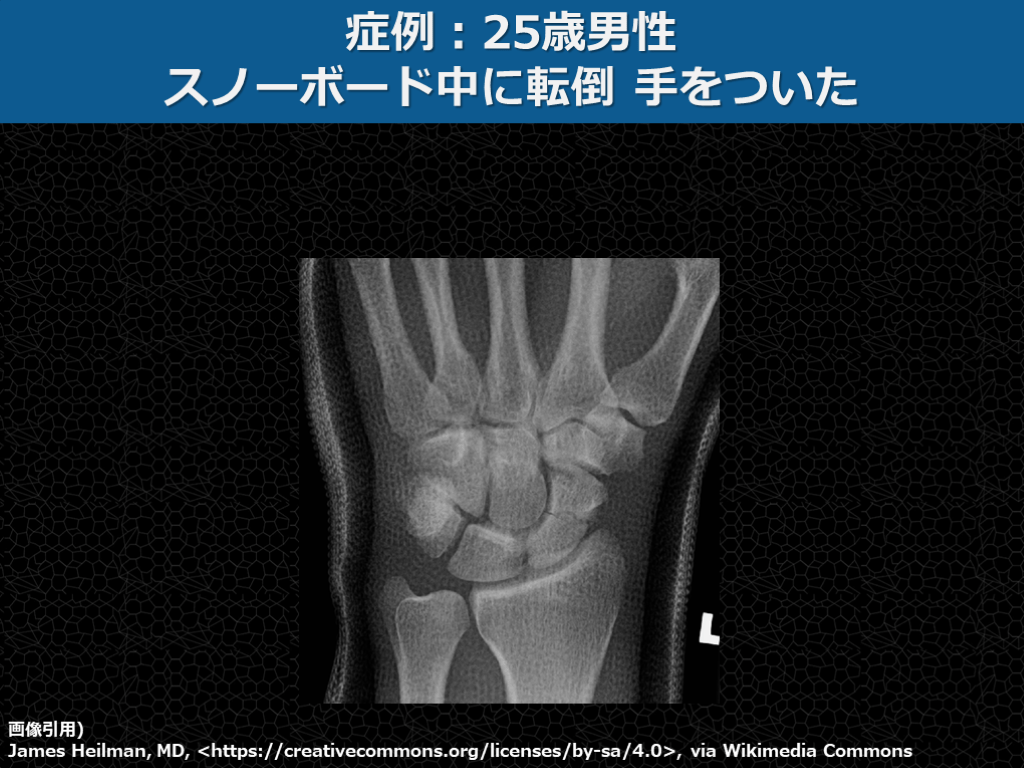

症例:25歳男性 スノーボード中に転倒 手をついた 画像引用) James Heilman, MD, <https://creativecommons.org/licenses/by-sa/4.0>, via Wikimedia Commons

症例:25歳男性 スノーボード中に転倒 手をついた 画像引用) James Heilman, MD, <https://creativecommons.org/licenses/by-sa/4.0>, via Wikimedia Commons 舟状骨骨折 鑑別を知らないと診断は難しい…

①年齢×受傷機転で鑑別を想起 参考に作成)増井伸⾼ 著 2019 ⾻折ハンター 中外医学社 ※FOOSH: fall on outstretched hand   覚えて鑑別のレパートリーを増やす →知らない骨折は見抜けない!